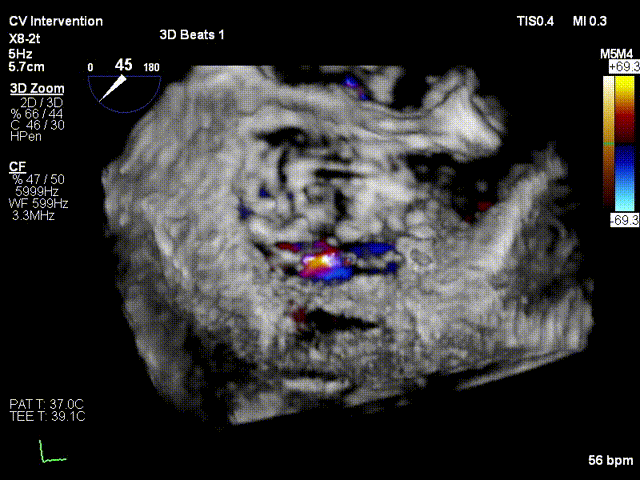

行TEE示:房间隔卵圆窝膨胀瘤改变;房间隔穿刺高度37mm;二尖瓣前叶 长度20.9mm,后叶长度10.9mm;二尖瓣面积4.94cm2;左冠状动脉内径增宽;收缩期 二尖瓣口偏心性反流束缩流颈宽度6.2mm,反流束起源于A1/P1及前交界,PISA定量反 流EROA=0.51cm2,舒张期二尖瓣口平均跨瓣压差1mmHg。

患者平卧导管床,常规消毒铺巾,呼吸机辅助呼吸,穿刺右侧股静脉,于经食道超声指导下穿刺房间隔,确认穿刺针位于左房后交换房间隔穿刺导管至左房, 再予super stiff置入左上肺静脉;退出房间隔导管后予16F预扩张鞘扩张右股静脉;于右股静脉沿Super stiff推送24F MitraClip steerable Guide Catheter于左房, 于3DTEE指导下,推送NTR Clip Delivery System至二尖瓣左房面,3DTEE确认12点钟 方向推送至二尖瓣左室面,重新调整DC handle使Clip Arm至11点钟方向。顺利捕捉 二尖瓣前叶A1及后叶P1区域,Gripper down后夹闭Clip Arm,3DTEE评估二尖瓣反流 由MR4+减少至1+,确认A1有效夹持长度8mm,P1有效夹持长度8mm,确认瓣叶夹持牢固, 释放瓣膜夹,3DTEE再次评估二尖瓣反流1+;退出MitraClip系统,3DTEE评估房间隔 穿刺口少量左向右分流,3DTEE评估房间隔 穿刺口少量左向右分流,未见右向左分流,未见心包积液,结束手术。